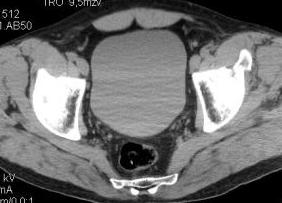

Уважаемые коллеги! Хотелось бы услышать ваше мнение. Мужчина 50л поступил с переломами костей таза. Закрытый перелом крыла подвздошной кости, переднего края вертлужной впадины справа.

Достаточно ли консервативного лечения, стоит ли беспокоиться о переднем крае? В приложении КТ.

Если уж делали КТ, то наверное сохранились сами срезы.